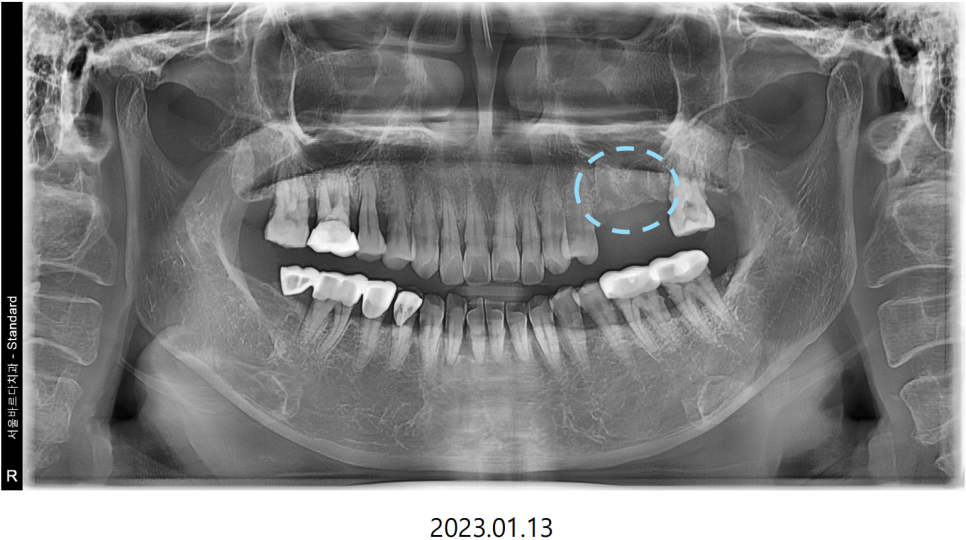

씹을때 먹먹하고 한쪽으로만 식사를 하신다는 이야기를 듣고

전반적으로 뼈와 치아 상태를 확인하는

파노라마 엑스레이를 촬영하여 보니

통증이 있다고 하는 왼쪽 위 큰어금니2개와

바로 그 앞의 작은어금니가 많이 흔들리는 상황이였습니다.

다수의 치아가 흔들리는 상황이였기에

치아의 뿌리를 조금 더 정밀하게 볼 수 있는

치근단 엑스레이와 CT를 추가적으로 촬영하였습니다.

치근단 엑스레이와 CT를 확인해본 결과

통증의 원인이 되는 큰어금니 하나는

뿌리쪽에서 뿌리 끝 염증이 생긴것을 확인했습니다.

이 뿌리 끝 염증이 커질수록 잇몸이 붓고

심하게는 뼈를 녹이게 되므로

주변 치아까지 영향을 미치게 됩니다.

뿌리에 생긴 낭이 뼈를 녹여

상악뼈 양이 얼마 남지 않은

모습을 확인할 수 있습니다.